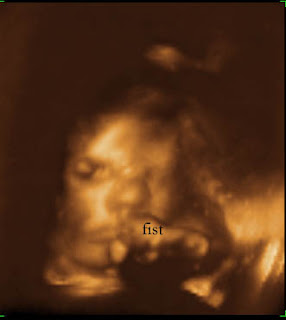

Here are some u/s pictures. Even though we had the 3D shot I don't think they came out that great. They weren't clear like I've seen some others and I couldn't compare Kayla's picture to the u/s and say she looked just like that! Her face was always pushed up against my placenta and appeared squished.

24 weeks and 5 days (the first 3 where all taken at the same visit)

You can just make out the nose and mouth

being a little shy and not wanting her picture taken (just like her mommy!)

35 weeks - she looks a little mad in this one!